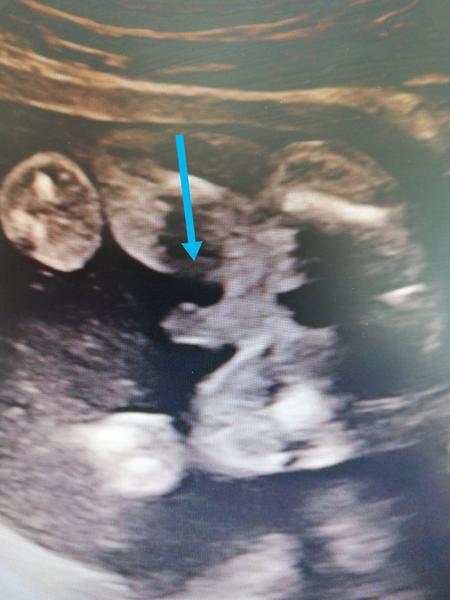

Od 13.tydne potvrzen chlapeček a 38. týden stále chlapeček a doufam, ze to tak i zůstane 😀

@michaela1990xx tak tady to je jasný 😁😁

@sarlotka18 taky mam fotku pytliku 🤣🤣